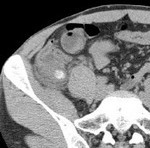

[画像診断]バージャー病(Buerger disease)の CT angiography